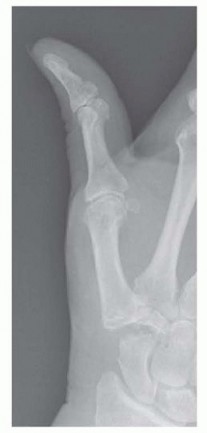

3. Capsulotomy and Metacarpal Base Preparation

With the radial artery safely protected, a longitudinal capsulotomy is performed directly over the midline of the CMC joint, extending proximally to expose the scaphotrapezial joint. The capsular flaps are elevated subperiosteally using a sharp Freer elevator or a small surgical blade. Heavy 3-0 Vicryl tag sutures or small sharp retractors are used to retract the capsular flaps, providing a panoramic view of the trapezial articulations.

Before attempting to excise the trapezium, it is highly advantageous to address the base of the thumb metacarpal. Using an oscillating microsagittal saw, a thin, 2-3 millimeter transverse sliver of bone is resected from the proximal articular surface of the metacarpal base.

Image

This maneuver serves three critical purposes: First, it removes the eburnated, osteoarthritic cartilage of the metacarpal. Second, it creates a flat, bleeding cancellous bone surface that will eventually interface with the tendon interposition. Third, and most importantly, it dramatically increases the working space within the joint, facilitating access to the distal pole of the trapezium and allowing for a much safer subsequent trapeziectomy.